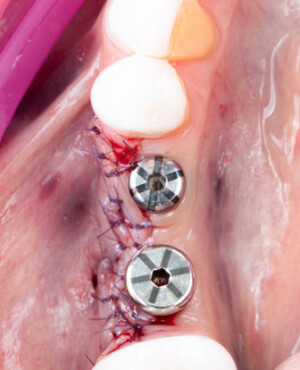

Aditia gingivală este o procedură chirurgicală ce corectează diverse probleme estetice și funcționale, cum ar fi recesiunea gingivală. În implantologia modernă, aditia de țesut moale este utilizată aproape în fiecare intervenție de inserție a implantului dentar pentru a asigura un aspect estetic natural și o bună integrare a implantului în cavitatea bucală.

Adiția osoasă are un rol crucial pentru poziționarea corectă și stabilă a implanturilor dentare. Clinica stomatologică Dr. Grossu din Chișinău promovează o abordare chirurgicală estetică și predictibilă, adaptată fiecărui caz în parte.